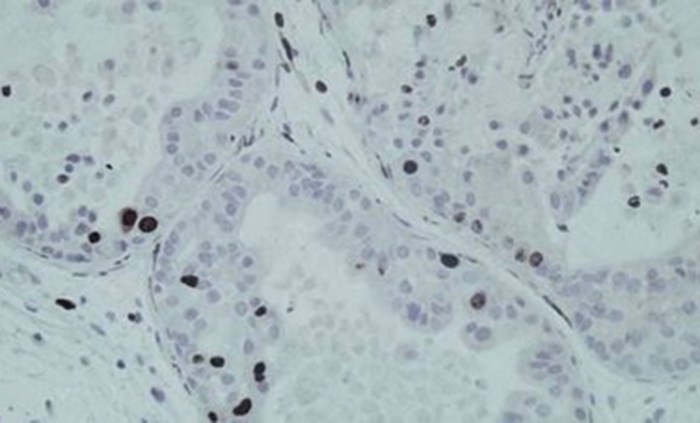

Descubren 187 nuevas variantes genéticas relacionadas con el cáncer de próstata

Un equipo científico de todo el mundo ha recopilado la lista más completa de variantes genéticas asociadas al riesgo de cáncer de próstata (451 en total, de las que 187 son nuevas) mediante un análisis del genoma completo que constituye la mayor y más diversa investigación sobre genética del cáncer de próstata realizada hasta la … Continuar leyendo Descubren 187 nuevas variantes genéticas relacionadas con el cáncer de próstata